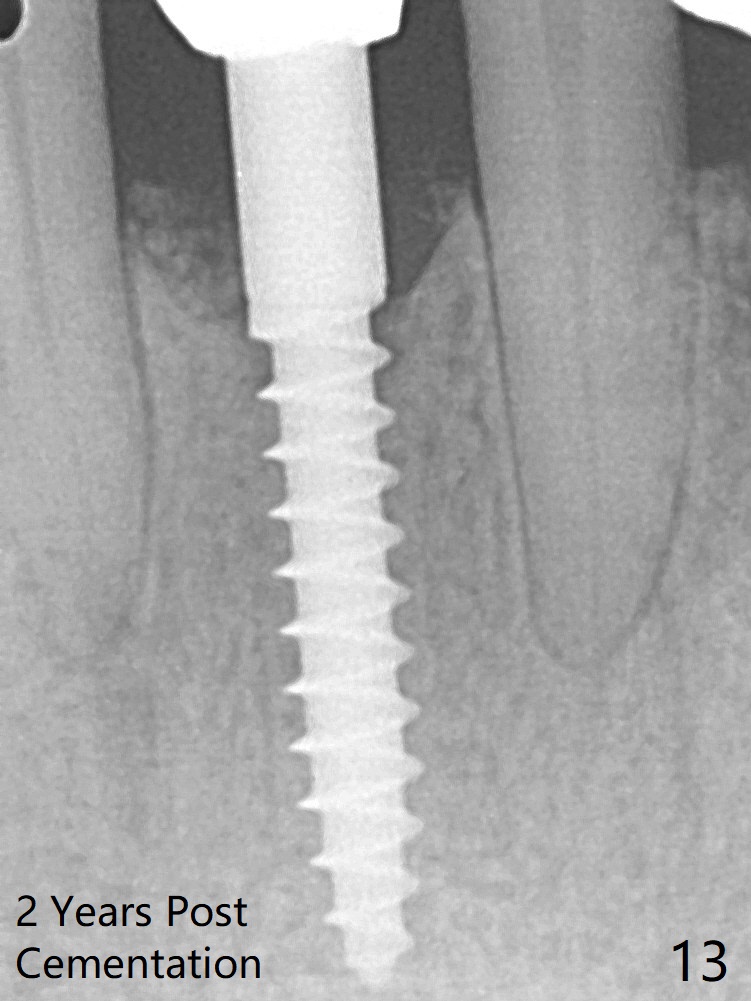

Because of the narrow flat ridge buccolingually, a 2.5x12(4) mm 1-piece implant is placed with >40 Ncm (Fig.8). With deeper placement of the implant, Vanilla graft is placed in 2 steps (Fig.9,10 *). No implant threads are exposed 10 months postop (Fig.11) or 2 years post cementation (Fig.13). Undermine the papilla between 24/25 and place bone graft next case.